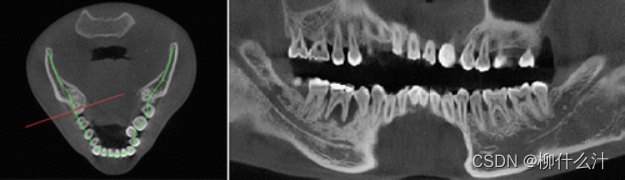

改造可以沿着手动或自动绘制的曲线进行。最常见的是沿牙弓绘制全景曲线,以生成一系列牙齿和骨骼的合成全景图(图00和01)。由于这些合成全景图像的厚度较小,通常不可能在一张图像中看到上下牙弓的情况。因此,通常需要为上、下牙弓分别绘制曲线(图02)。另外,可以计算出这些合成全景图的射线和,类似于从全景X光片上获得的图像。图23显示了不同厚度的合成全景堆叠的射线和全景图像。

不同厚度下的合成射线总和图像。

除了合成全景图像外,还可以从垂直于全景曲线的线条中得到截面图像。

左图:横断面图像的位置,垂直于全景曲线,显示在一个轴向切片上。右图:沿曲线不同位置的横断面图像。